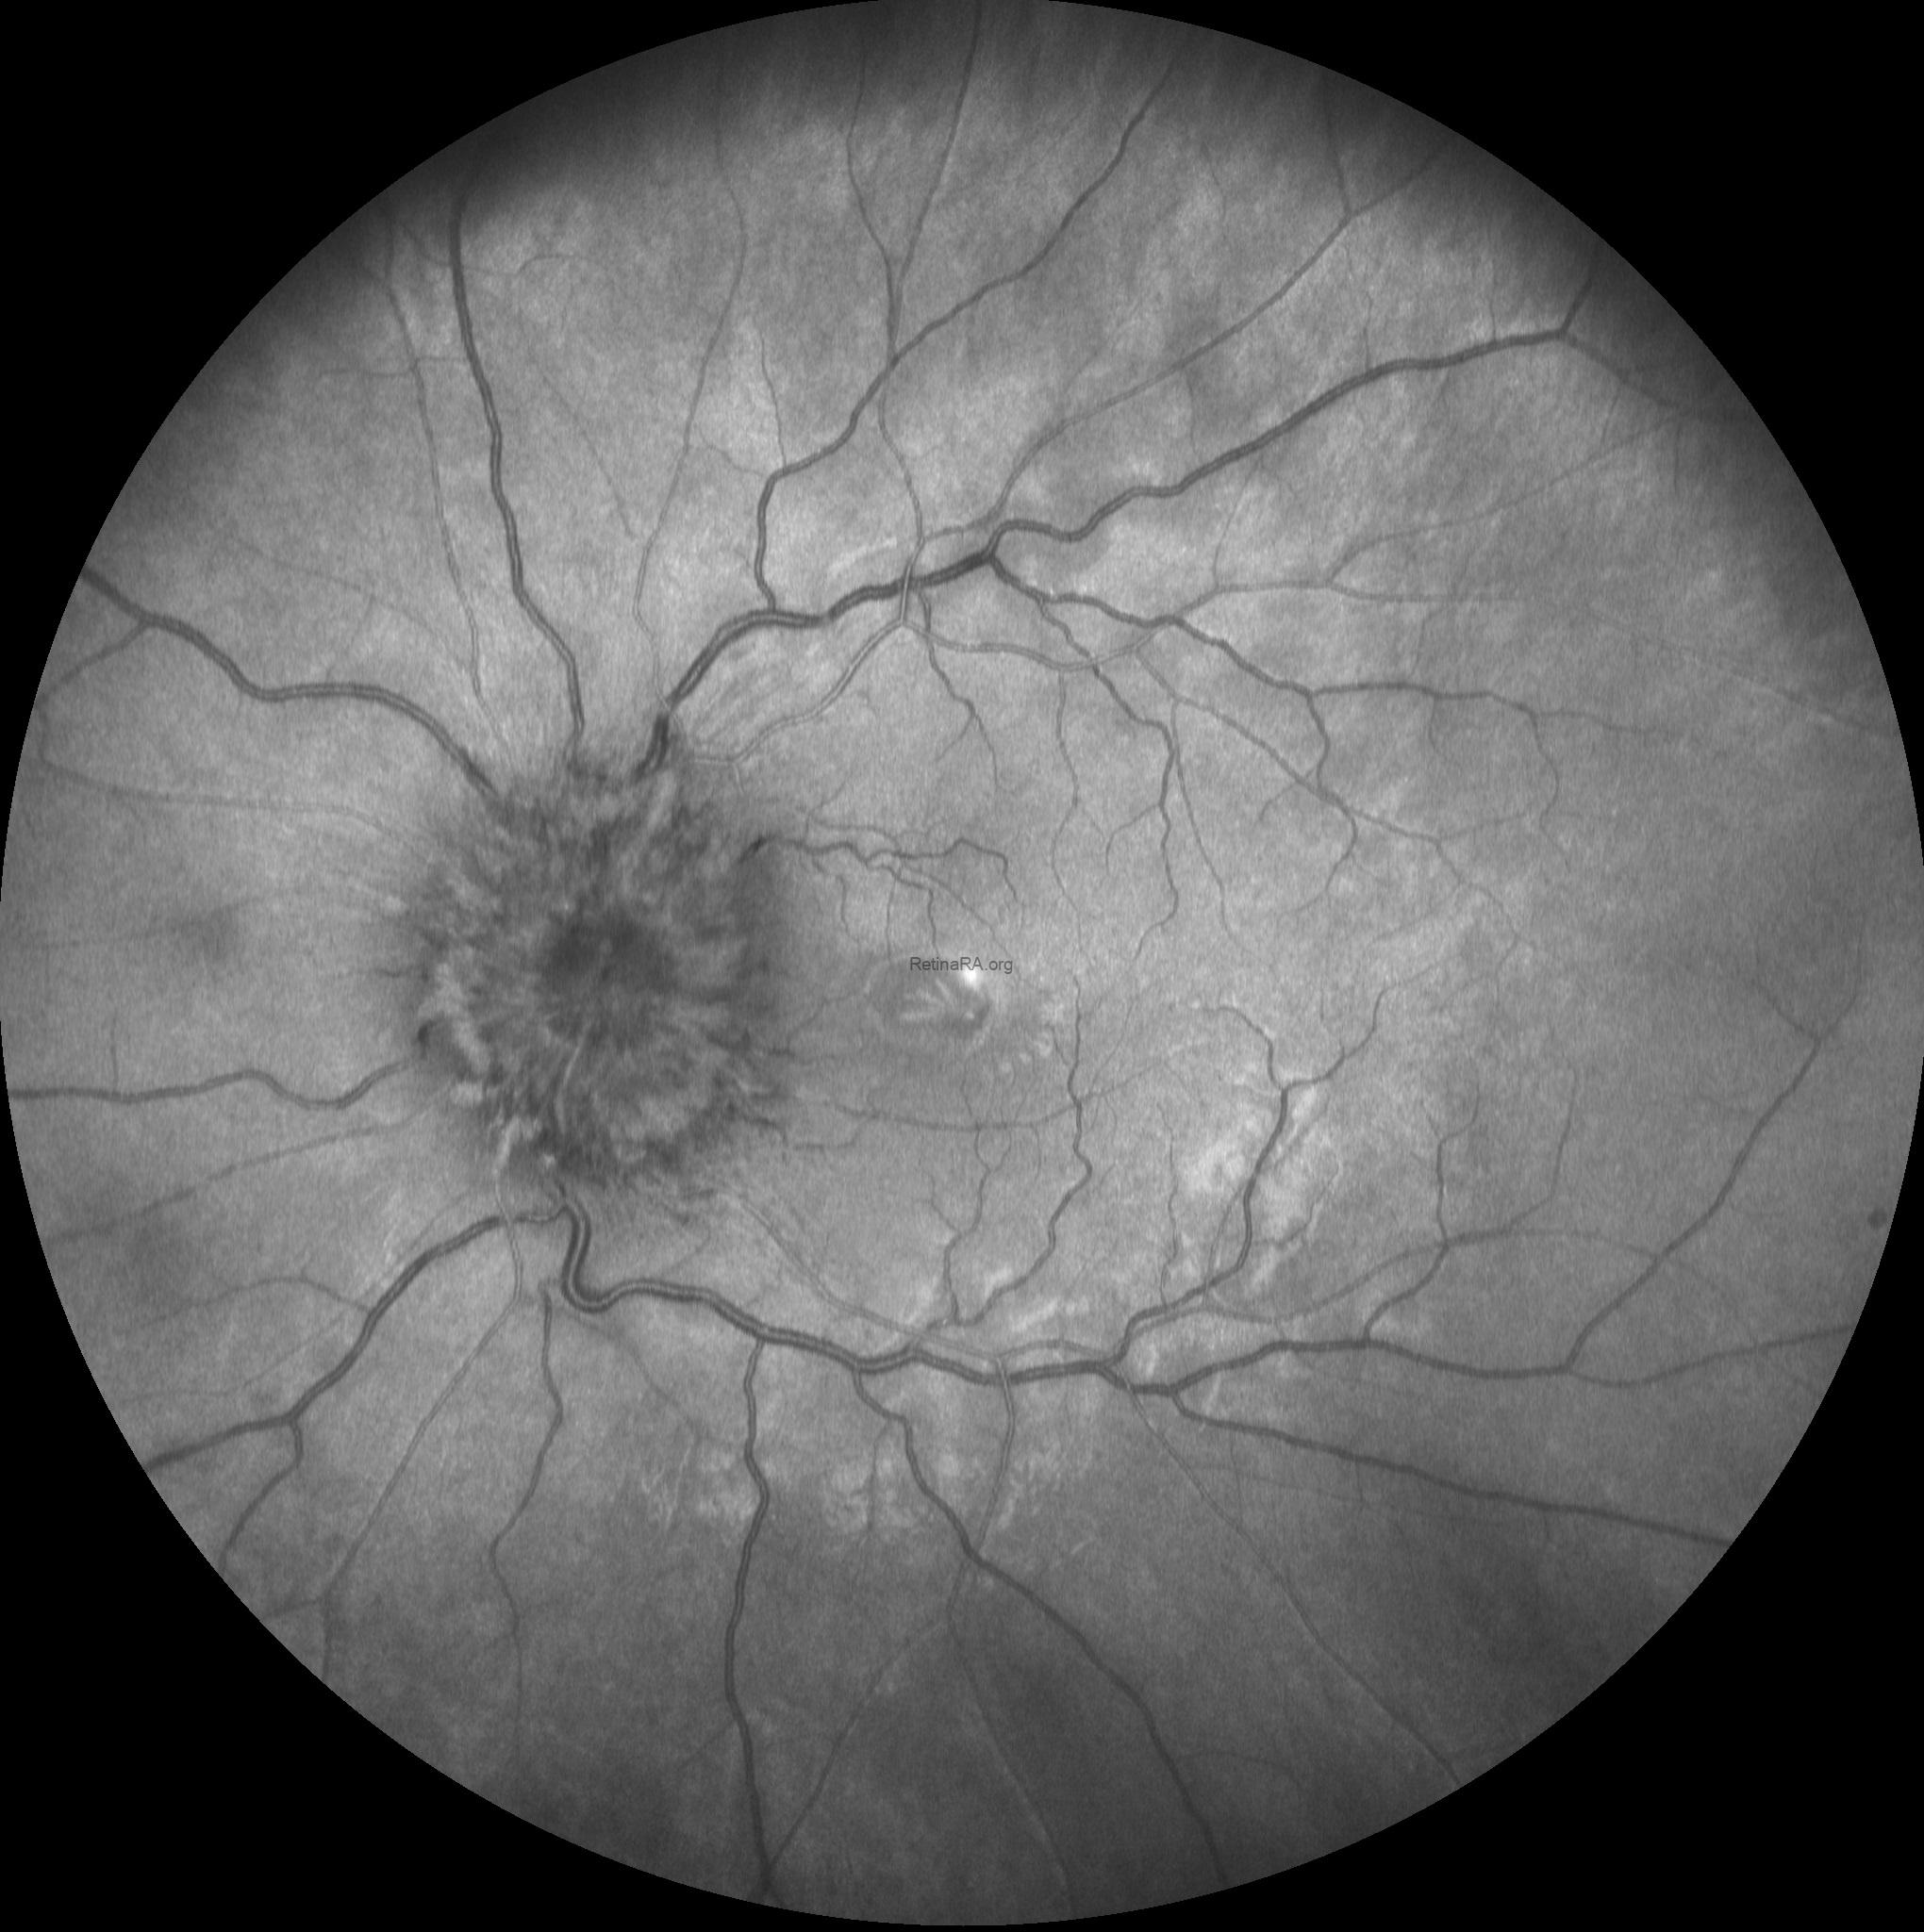

Multicolor and infrared fundus images revealed bilateral severe optic disc swelling, elevation of the disc with blurred margins, smoothly demarcated peripapillary halo, optic nerve head hyperemia, peripapillary hemorrhages, and obscuration of cup and major vessel (Grade 5 according to Frisén Scale).

Based on the optic disc appearence, the patient was diagnosed as severe papilledema and consulted to the neurology department. After neurological asessment including craniyal computed tomography the patient was diagnosed as glioblastoma multiforme.